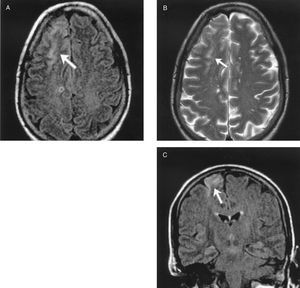

En las primeras 48 h, se realizó un primer estudio de neuroimagen con TC craneal en 50 pacientes. Sólo un estudio mostró hemorragia cerebral, a pesar del potencial riesgo que todos los pacientes sufren por precisar anticoagulación a dosis altas durante el procedimiento quirúrgico y la coagulopatía secundaria al uso de un circuito extracorpóreo. Destaca que, en este estudio inicial, en 35 (70%) pacientes no se observaron hallazgos relevantes que pudieran justificar la clínica. De éstos, en 23 pacientes persistió la clínica neurológica más de 24 h y se realizó un segundo estudio de control para buscar posibles lesiones isquémicas (a los 7-10 días, bien en UCI o planta de hospitalización): 5 estudios demostraron regiones isquémicas coherentes con la clínica; en los 18 restantes, la TC no presentó hallazgos, por lo que también se realizó una RMC. De este último grupo de pacientes, 11 presentaron déficit motor focal; en todos los pacientes, excepto en uno (que clínicamente sólo presentó una disfasia mixta transitoria), en la RMC encontramos áreas de infarto agudo o subagudo en diferentes localizaciones, fundamentalmente de pequeño tamaño, en distribución periférica, en territorios frontera, que podrían justificar los hallazgos clínicos (tabla 1). Estas imágenes aparecen hiperintensas en las imágenes de las secuencias T2 y secuencia FLAIR (secuencia de supresión de líquido cefalorraquídeo). También se realizó RMC en 4 pacientes con encefalopatía leve-moderada y sin hallazgos radiológicos en la TC; de éstos, 1 estudio no mostró alteraciones significativas, pero en los otros 3 se observaron lesiones similares a las descritas previamente en los pacientes con ictus, mostrando lesiones hiperintensas sugerentes de infartos agudos o subagudos. Por último, se realizó RMC en 3 pacientes con una clínica de encefalopatía severa y coma superior a 48 h; en ellos se objetivaron áreas múltiples de infarto a nivel cortical, que aparecieron como una hiperintensidad cortical global, con edema en las circunvoluciones. En las figuras 3 y 4 se presentan ejemplos de RMC en ictus posquirúrgicos, con TC de cráneo sin hallazgos patológicos. En la figura 5 se observa la RMC de un paciente con despertar prolongado y posterior afectación del nivel de conciencia durante aproximadamente 36 h y TC craneal sin hallazgos.

Fig. 3. Paciente sometido a sustitución valvular aórtica. Hemiparesia izquierda y disminución del nivel de conciencia. Dos tomografías computarizadas craneales sin hallazgos. En la resonancia magnética cerebral se observa una lesión hiperintensa en región frontoparietal derecha en las secuencias T2 y FLAIR.

Fig. 4. Paciente con sustitución valvular mitral. Hemiparesia izquierda. Tomografía computarizada craneal sin hallazgos. En la resonancia magnética cerebral se observan lesiones hiperintensas en región frontoparietal derecha en las secuencias T2 y FLAIR.